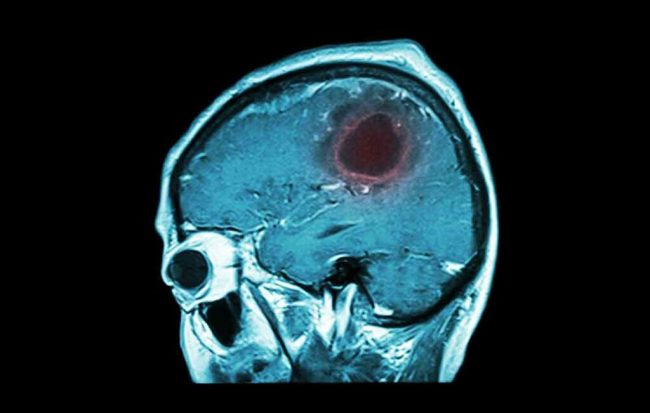

Όγκος στον εγκέφαλο